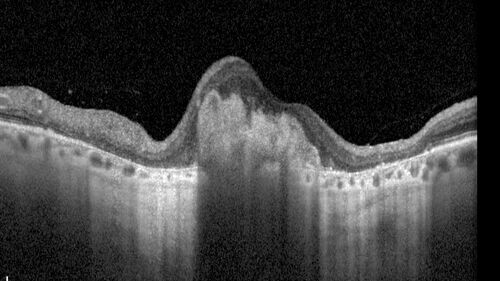

78 year old female with vision loss for 1 week and old macular scar. Images show BRAO with plaques and FA shows occlusion.

BRAO_126199_071725_05.jpg

BRAO and macular scar - plaques in vessel and video